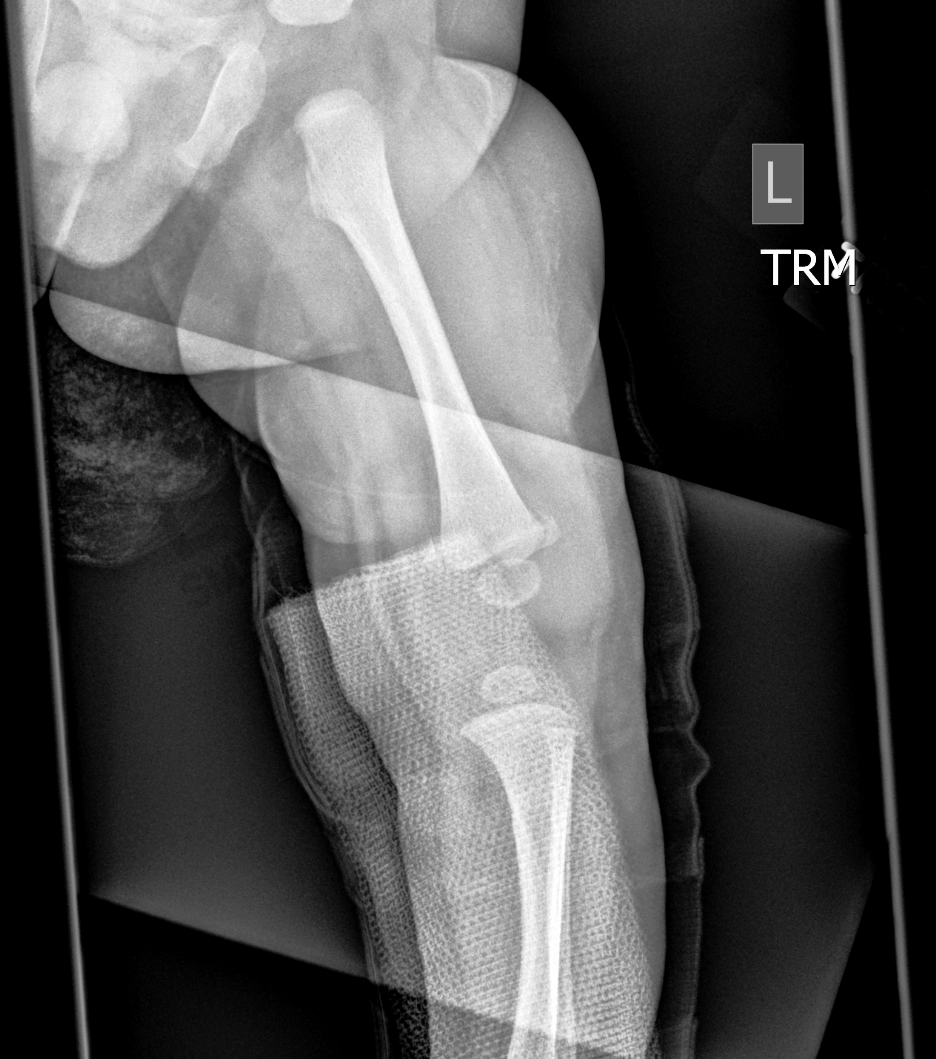

Info Images Findings Impression Reco/Acuity Case Images View Images / Launch Visage Case Notes History 2-month-old presents with decreased right arm movement, increased fussiness, and increased sleepiness for 2 days. Suspected non-accidental trauma. Exam Skeletal survey Prior Study none Dicom View Reference Material

Section 1 Submit Findings CB1550 Findings Skeletal Survey - Technique Check Skull AP/Lat Yes No Cervical and Thoracolumbar spine Yes No Chest X-Ray Yes No Ribs – Left/Right Oblique Yes No Abdominal X-Ray Yes No Pelvis with both hips Yes No Bilateral Humerus, Forearm, Hand Yes No Bilateral Femur, Tibia/fibula, feet Yes No Any additional lateral views of the extremities Yes No The exam is over or under penetrated. Yes No The exam may or may not be limited by overlying structures or soft tissues, body habitus, patient positioning, support devices, or motion. Yes No The area of concern is indicated by the patient, technologist, or care provider. Yes No The area of concern is included on the exam. Yes No Soft Tissues There is soft tissue swelling, indistinctness of fat/muscle planes, gas, or laceration in the area of clinical concern. Yes No There is an effusion, fat pad displacement, or fat fluid level. Yes No There is a radiodense or lucent foreign body. Yes No There are other densities, calcifications, post-surgical changes, or support devices in the soft tissues. Yes No Any support lines/tubes. Yes No Bone There is a break or interruption of the continuity of the cortical or cancellous bone. Yes No There is overriding of the trabeculae with apparent sclerosis. Yes No There is displacement of a fracture fragment. Yes No There is bowing of the bone in addition to the fracture at the apex of the bowed bone concerning for the greenstick. Yes No There is a spiral fracture of the leg concerning for toddler’s fracture. Yes No There is abnormal angulation or bulging of the cortical surface relative to the normal cortex which could be from a buckle or torus fracture. Yes No There is a displaced fragment which may be from avulsion by a tendon, ligament, or joint capsule or from a comminuted or other fracture. Yes No The stress trabeculae or other trabeculae of the cancellous bone are interrupted or otherwise abnormal. Yes No There is subperiosteal or endosteal reaction which could indicate a healing or subacute fracture or other abnormality. Yes No There is hard/soft callus formation. Yes No There is remodeling of the bone. Yes No There is a corner fracture or metaphyseal lesion that could be from nonaccidental trauma. Yes No There are multiple fractures of different ages. Yes No There are vertebral body/spinous process fractures. Yes No There are rib fractures. Location - posterior or lateral. Yes No There is scapular/sternal fracture. Yes No There are fractures of the digits. Yes No There are wormian bones. Yes No There are intrasutural bones. Yes No There is metaphyseal abnormality (lucencies, increased density, erosion) which may be from something other than injury such as stress, metabolic disease (e.g. rickets with loss or distortion of the zone of the provisional calcification), neoplasm (e.g. leukemia), heavy metals, inflammation, or infection. Yes No There are metaphyseal spurs. Yes No There are bony deformities involving multiple bones. Yes No The bones are gracile. Yes No There are non-healing fractures. Yes No There is/are focal or multifocal lytic/lucent, blastic/sclerotic or mixed density lesion(s) or other abnormality. Yes No Overall bone density is increased or decreased with or without thinning or thickening of the cortical or cancellous bone. Yes No Growth plates, ossification centers, apophyses The growth plate(s) is/are abnormal. Yes No There is widening of the physis from a fracture with or without displacement of the epiphysis (Salter-Harris I). Yes No There is a fracture through the physis which then extends into the metaphysis with or without angulation or displacement (S-H II). Yes No There is a fracture through the physis which then extends into the epiphysis and is intra-articular, with or without angulation or displacement (S-H III). Yes No There is a fracture through the metaphysis, physis, and epiphysis which extends into the joint space with or without angulation or displacement (S-H IV). Yes No There is narrowing of the physis from a compression fracture (S-H V). Yes No The apophysis, epicondyle, secondary ossification center, or accessory ossicle is displaced or otherwise abnormal. Yes No The ossification centers are underdeveloped. Yes No Joints and alignment There is an effusion, fat pad displacement, or fat fluid level. Yes No The epiphysis or subchondral bone is fractured, interrupted, flattened, compressed, impacted, displaced, or otherwise abnormal. Yes No There is an intra-articular loose body or chondrocalcinosis. Yes No The joint is widened, narrowed, dislocated, malaligned, or incongruent. Yes No There is pseudoarthrosis. Yes No Other findings There are developmental changes or other anatomic variants or other existing conditions that may or may not be contributing to symptoms which can or should be further evaluated non-emergently or are otherwise incidental. Yes No The remainder of the exam is abnormal for age. Yes No The lungs show focal airspace opacity. Yes No There is pneumothorax. Yes No There is organomegaly. Yes No There is intra-abdominal calcification. Yes No There is displacement of the bowel loops. Yes No There is free intraperitoneal air. Yes No The bowel loops are dilated/obstructed. Yes No There is paraspinal soft tissue abnormality. Yes No